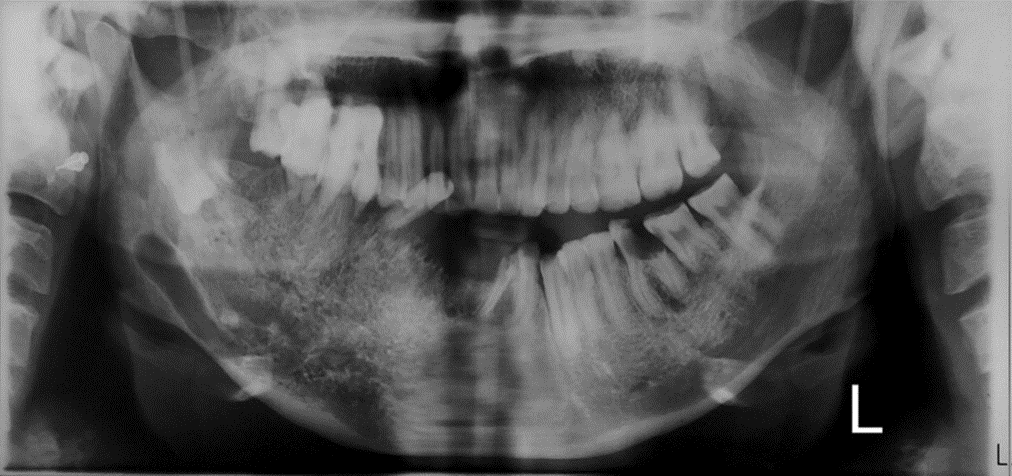

Las lesiones mixtas o heterogeneas son un grupo de lesiones que se presentan con menor frecuencia que las lesiones radiolúcidas en los huesos maxilares siendo tan raras como las lesiones radiopacas, y abarcan un grupo de lesiones de origen odontogénicas y no odontogénicas. Este último grupo incluye trastornos hereditarios y del desarrollo, osteomielitis y tumores...

La radiografía panorámica (PAN) y la tomografía computarizada de haz cónico (TCCB) son dos modalidades radiográficas utilizadas en el diagnóstico, la planificación del tratamiento y el manejo de las enfermedades orales y maxilofaciales. No solo muestran las características de las lesiones en las imágenes, sino que también guían a los médicos para que realicen los...